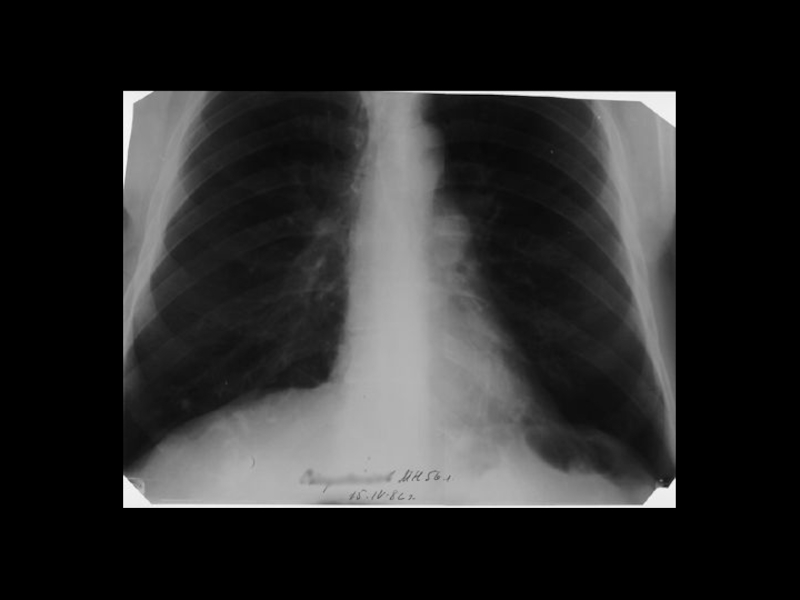

Центральный рак легкого

ЛУЧЕВАЯ ДИАГНОСТИКА РАКА ЛЕГКОГО